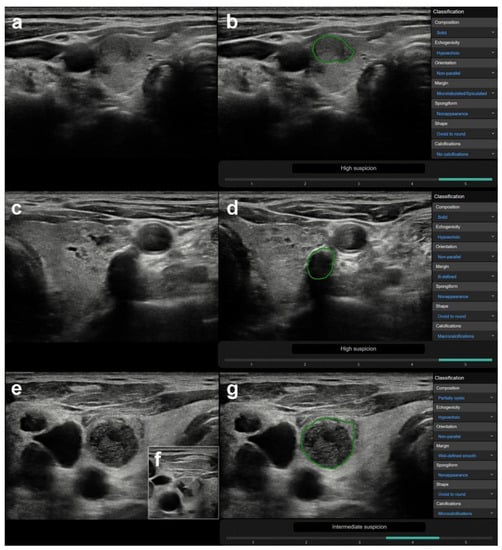

3.1. US Features or Entities Associated with CAD System Misdiagnosis Including Mimicking Lesions